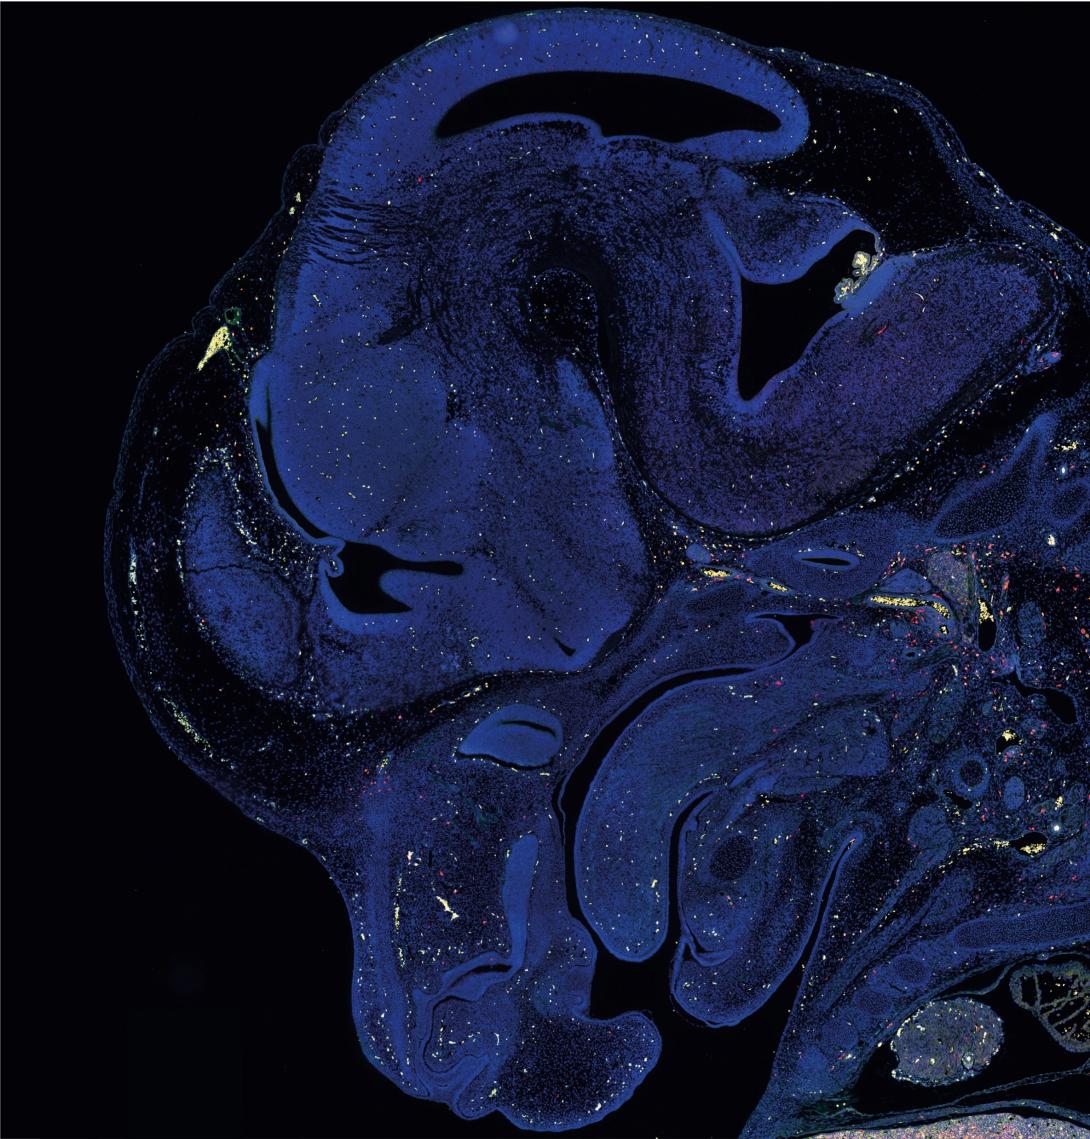

A slice of brain tissue stained with a blue marker

Credit: David Munro, Priller Lab